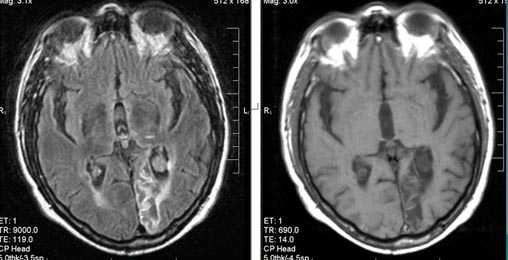

Первые часы ОНМК. Изменения в области правого островка демонстрирует только программа DW insult.

Бассейн кровоснабжения левой верхней мозжечковой артерии, острая стадия НМК.

Зона подострого ишемического НМК, в бассейне правой средней мозговой артерии. В режиме Т1 визуализируется симтом «вуалирования»- изоинтенсивность МР-сигнала.

Подострая стадия ишемического НМК. При внутривенном контрастировании определяется накопления КВ в бороздах на уровне зоны ишемии (гиральный тип усиления).

Зона хронического ишемического НМК, в бассейне левой задней мозговой артерии.

Ишемическое ОНМК, ствол мозга (подострый период)